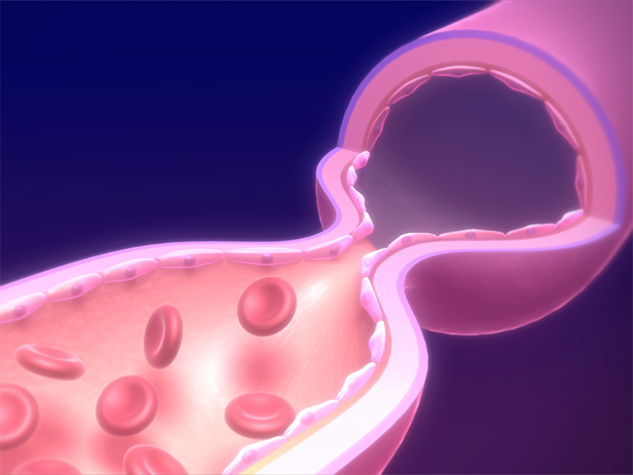

血管の収縮には、大きく分けると、「正常な収縮」と「異常な収縮」の2種類があります。

私たちの血管は、収縮と弛緩(しかん)を繰り返し、血流や血圧を一定に保っています。これが「血管の正常収縮」で、生命の維持になくてはならないものです。 血管を動かす筋肉組織(血管平滑筋細胞)内のカルシウムイオン濃度によって調節され、そのメカニズムは生物学の大原則として知られています。

血管の正常収縮時

血管の正常収縮時は血液がグングン流れる